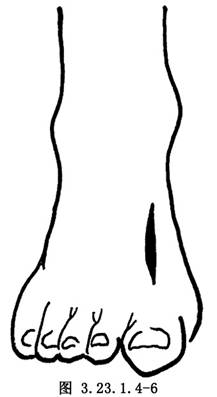

1.切口 以跖骨骨折部为中心,做一长3~4cm背侧纵切口(图3.23.1.4-6)。沿皮肤切口线切开深筋膜和骨膜,做骨膜下剥离,显露出跖骨骨折的近侧段和远侧段(图3.23.1.4-7)。